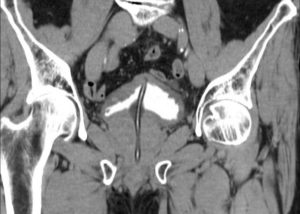

- Проведение трансвагинального ультразвукового исследования. В таком случае можно обнаружить небольшую ретенционную капсулу, которая не сообщается с уретральным каналом.

- Проведение рентгенологической диагностики. Необходимо для дифференциального анализа парауретрального новообразования.

- Проведение магнитно-резонансной томографии. Наиболее точный метод исследования кист, позволяющий детально оценить их анатомию.

На основании уретроцистоскопии и результата ультразвука ставят точный диагноз. УЗИ менее травматично, но иногда его бывает недостаточно. В редких случаях используют дополнительное исследование на аппарате МРТ.